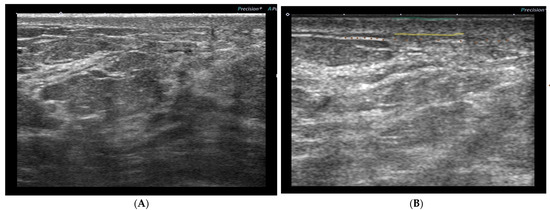

3.3. Ultrasound Protocol

3.4. US Skin Parameters and Locations of the Measurements

3.5. Ultrasonographic Skin Toxicity Changes